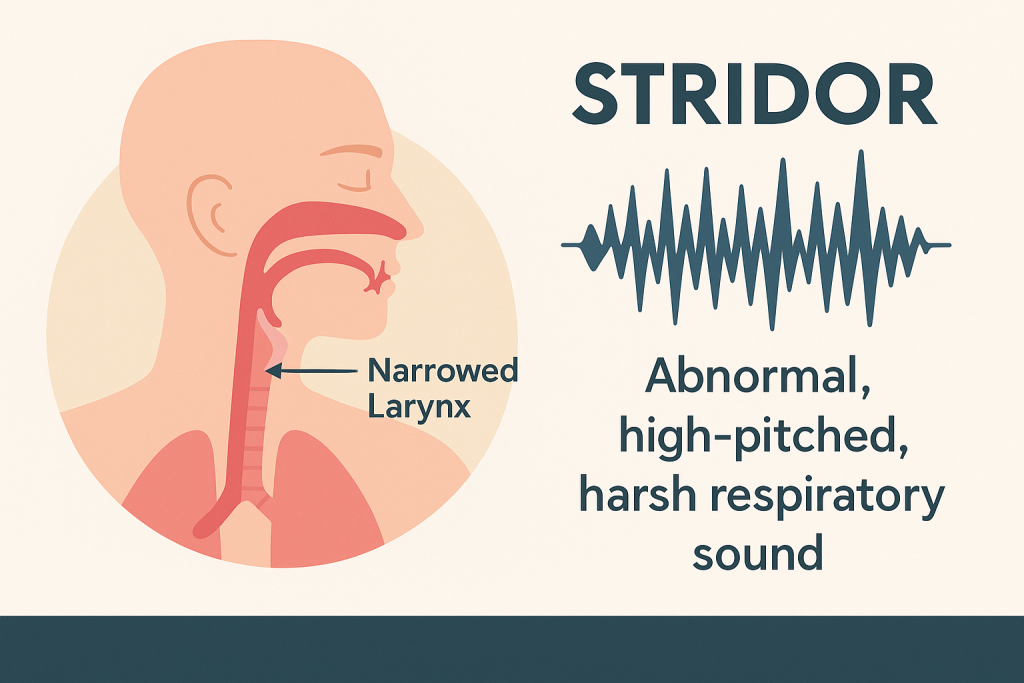

Stridor (સ્ટાઇડર):

- સ્ટ્રાઇડર (Stridor) એ એક અબનોર્મલ હાઈ-પિચ્ડ (High-pitched) બ્રીધીન્ગ સાઉન્ડ છે, જે સામાન્ય રીતે ઇન્સ્પિરેશન (Inspiration) દરમિયાન સાંભળાય છે.

આ અવાજ એ સમયે બને છે જ્યારે અપર એરવે (Upper Airway) – ખાસ કરીને લેરિંક્સ (Larynx) અથવા ટ્રેકિયા (Trachea) – નેરો (Narrowed)થઈ જાય છે અથવા ઓબ્સ્ટ્રક્ટેડ (Obstructed) થાય છે. - એટલે કે, Stridor = Inspiratory high-pitched harsh sound due to upper airway obstruction.